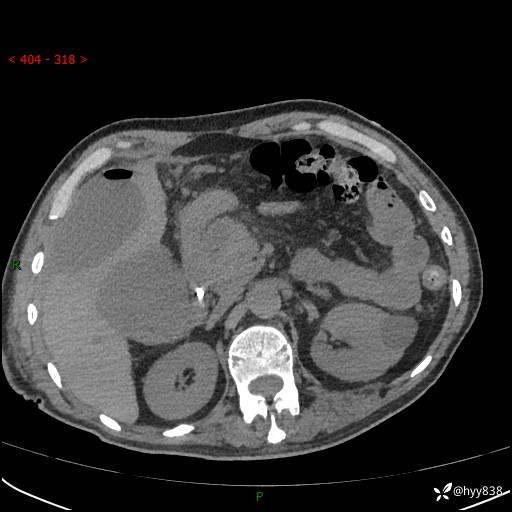

腹部CT平扫

增强